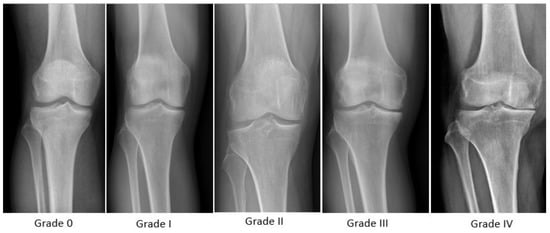

| Kellgren and Lawrence KOA Classification System | ||||

| Grade 0 | No radiological findings of OA | |||

| Grade I | Doubtful joint space narrowing and possible osteophytic lipping | |||

| Grade II | Certain osteophytes and possible joint space narrowing | |||

| Grade III | Moderate multiple osteophytes, certain narrowing of joint space, some sclerosis and possible deformity of bone ends | |||

| Grade IV | Large osteophytes, marked narrowing of joint space, severe sclerosis, and certain deformity of bone ends | |||